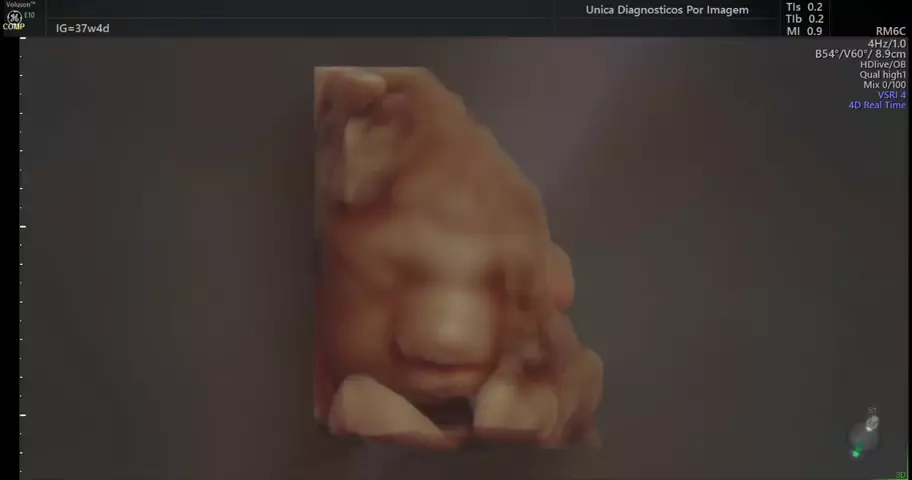

ultrassom 4D obstetrico.